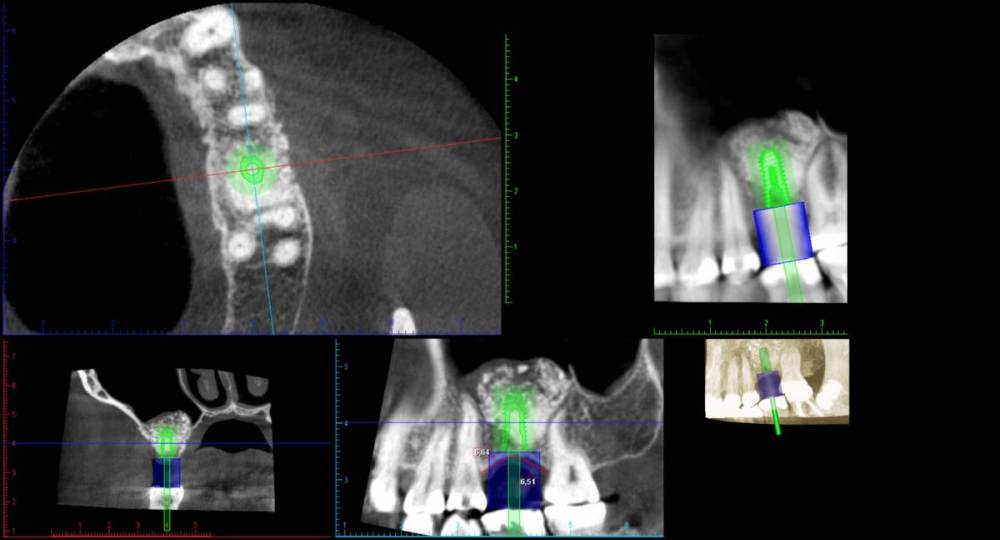

Ponchik Опубликовано 7 апреля, 2021 Поделиться Опубликовано 7 апреля, 2021 Добрый день. В августе прошлого года делал синуслифтинг (биоосс) Месяц назад поставил имплантант. Сегодня пациент пришел с жалобами на небольшую боль в области верхней челюсти. Сначало болело справа, потом слева(где работа) а сегодня прошло. В области имплантата свищ на верхушке гребня. Эксудат (уже чуть-чуть). Думаю имплантант убирать, весь материал убирать (как весь убрать пока не решил). Через полгода новый синуслифтинг и т.д. Но человек слаб и я тешу себя надеждой может не всё пропало? Добавил скрин перед имплантацией и скрин сегодня. На момент имплантации делалось ОПТГ, не информативное. Ссылка на комментарий

Ponchik Опубликовано 9 апреля, 2021 Автор Поделиться Опубликовано 9 апреля, 2021 20 часов назад, Женька сказал: Может это не совсем подходит к вашей ситуации, но где-то я слышал, что И.Урбан при развалившихся сосисках и цитопластах моет это всё стерильным физ раствором, до чистых промывных вод. Эффект - он всё равно получает плюс несколько мм к дефекту. Думаю в синусе можно делать также, только вот как это вымыть кроме как через ревизию? Я думал, удалить имплант и что ложкой смогу собрать - на выход, а там смотреть. 17 часов назад, Дмитрий Л. сказал: Сперва осторожно поставьте формирователь, вдруг это заглушечный свищ. Сегодня посмотрел, слизистая розовая и радостная, ничего не болит. не течет, все разрезы закрылись. Решил посмотреть (струсил всё убирать). Допьёт АБ, и через пару недель снова КЛКТ. Если конечно свищей не будет. А выкручивать заглушку не решился, срок 4 недели ((( Попробовал имплант - явно не двигается. 21 час назад, Jayseebrawn сказал: Мое мнение убирать имплант и чистить графт, по скольку он инфицирован Тоже думаю этим и закончится, но хочется чуда. Люди ходят к экстрасенсам, а я говорю кыш микрофлоре в графте. Ссылка на комментарий

Карен Аванесов Опубликовано 10 апреля, 2021 Поделиться Опубликовано 10 апреля, 2021 На стартовом кт. изначально не очень картинка, скорее всего, графт не организован, можно все убрать более предсказуемо будет, можно только имплантат, тогда быть может обойдется без повторного синуслифтинга. Судя по второму кт, жуткого прям такого воспаления нет, если пациент к Вам лоялен, консервативный вариант может иметь место. 1 Ссылка на комментарий

Sergiosse Опубликовано 21 апреля, 2021 Поделиться Опубликовано 21 апреля, 2021 В пазухе,похоже хронический гайморит. Я бы убрал имплант, сделал кюретаж, промыл, консервативное ведение. Через месяцок повторный снимок и решать что делать дальше? убирать остатки графта или ставить имплантант а то, что осталось. Ссылка на комментарий

Ponchik Опубликовано 16 июня, 2021 Автор Поделиться Опубликовано 16 июня, 2021 Сегодня поставил формирователь с торком 30-35. Подвижности нет. Обнаженных витков имплантата нет. Толщина слизистой 5-5.5 мм. Прикреплёнки 2-4мм. Снимков правда нет. 2 1 Ссылка на комментарий